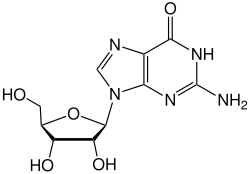

- (VII) Вирусы, содержащие частично двуцепочечную, частично одноцепочечную ДНК[150][151] и имеющие в своём жизненном цикле стадию синтеза ДНК на матрице РНК, ретроидные вирусы (например, вирус гепатита B)[152].